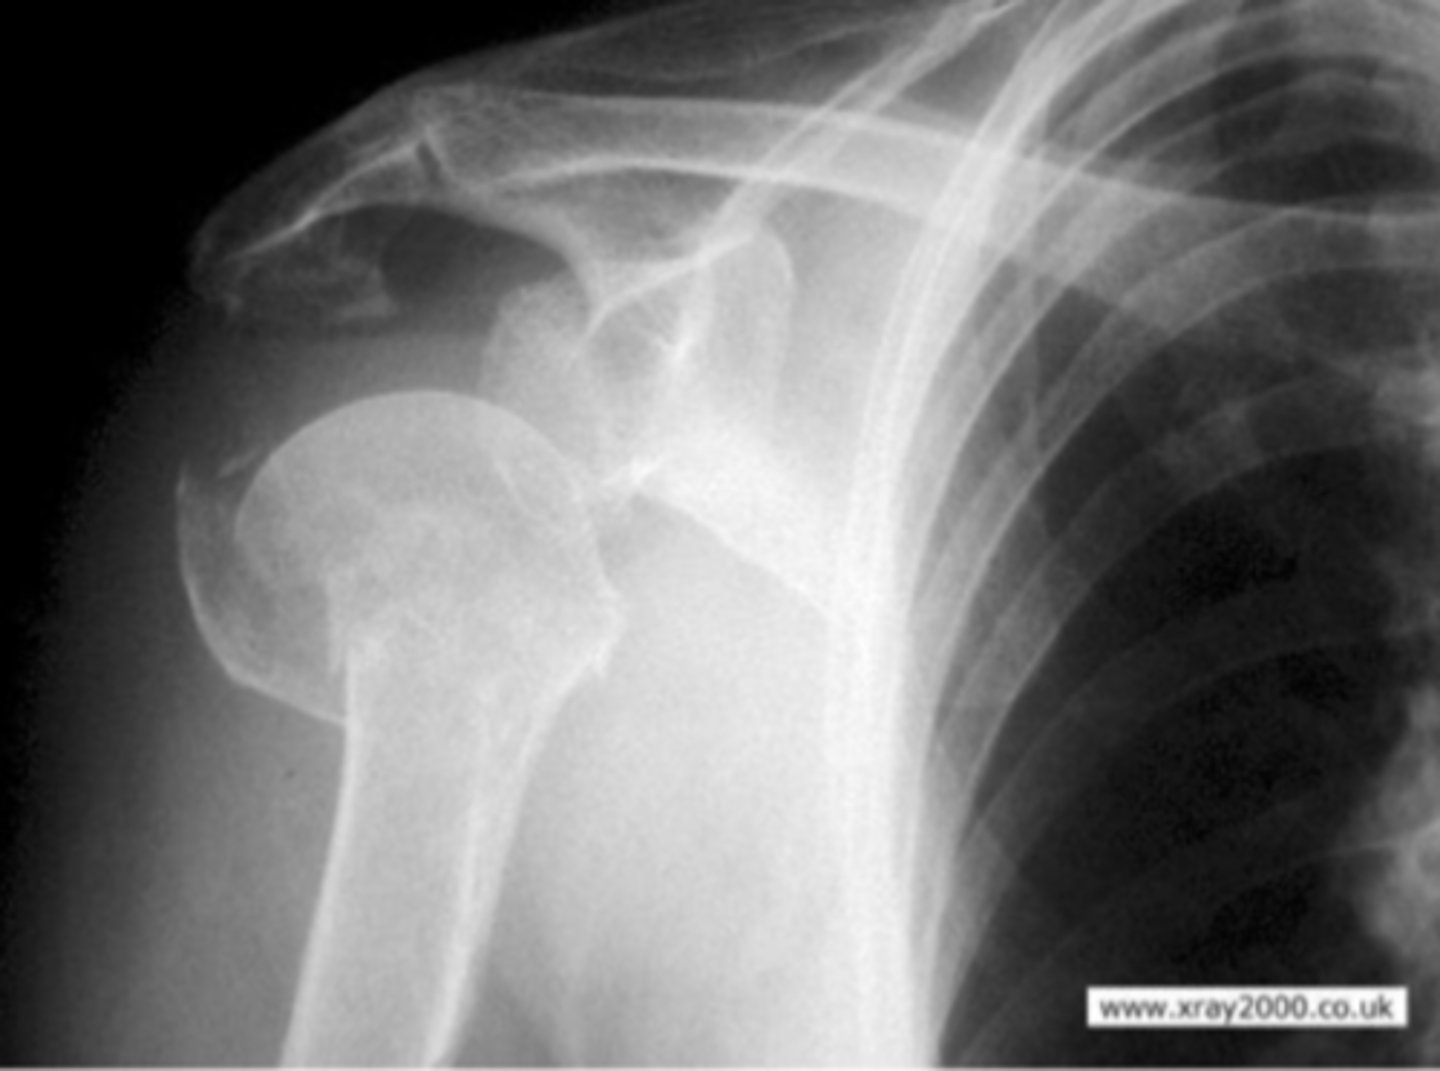

AP of the right shoulder

What view does this show?

Anterior/Inferior displacement of the GHJ

What is the issue?